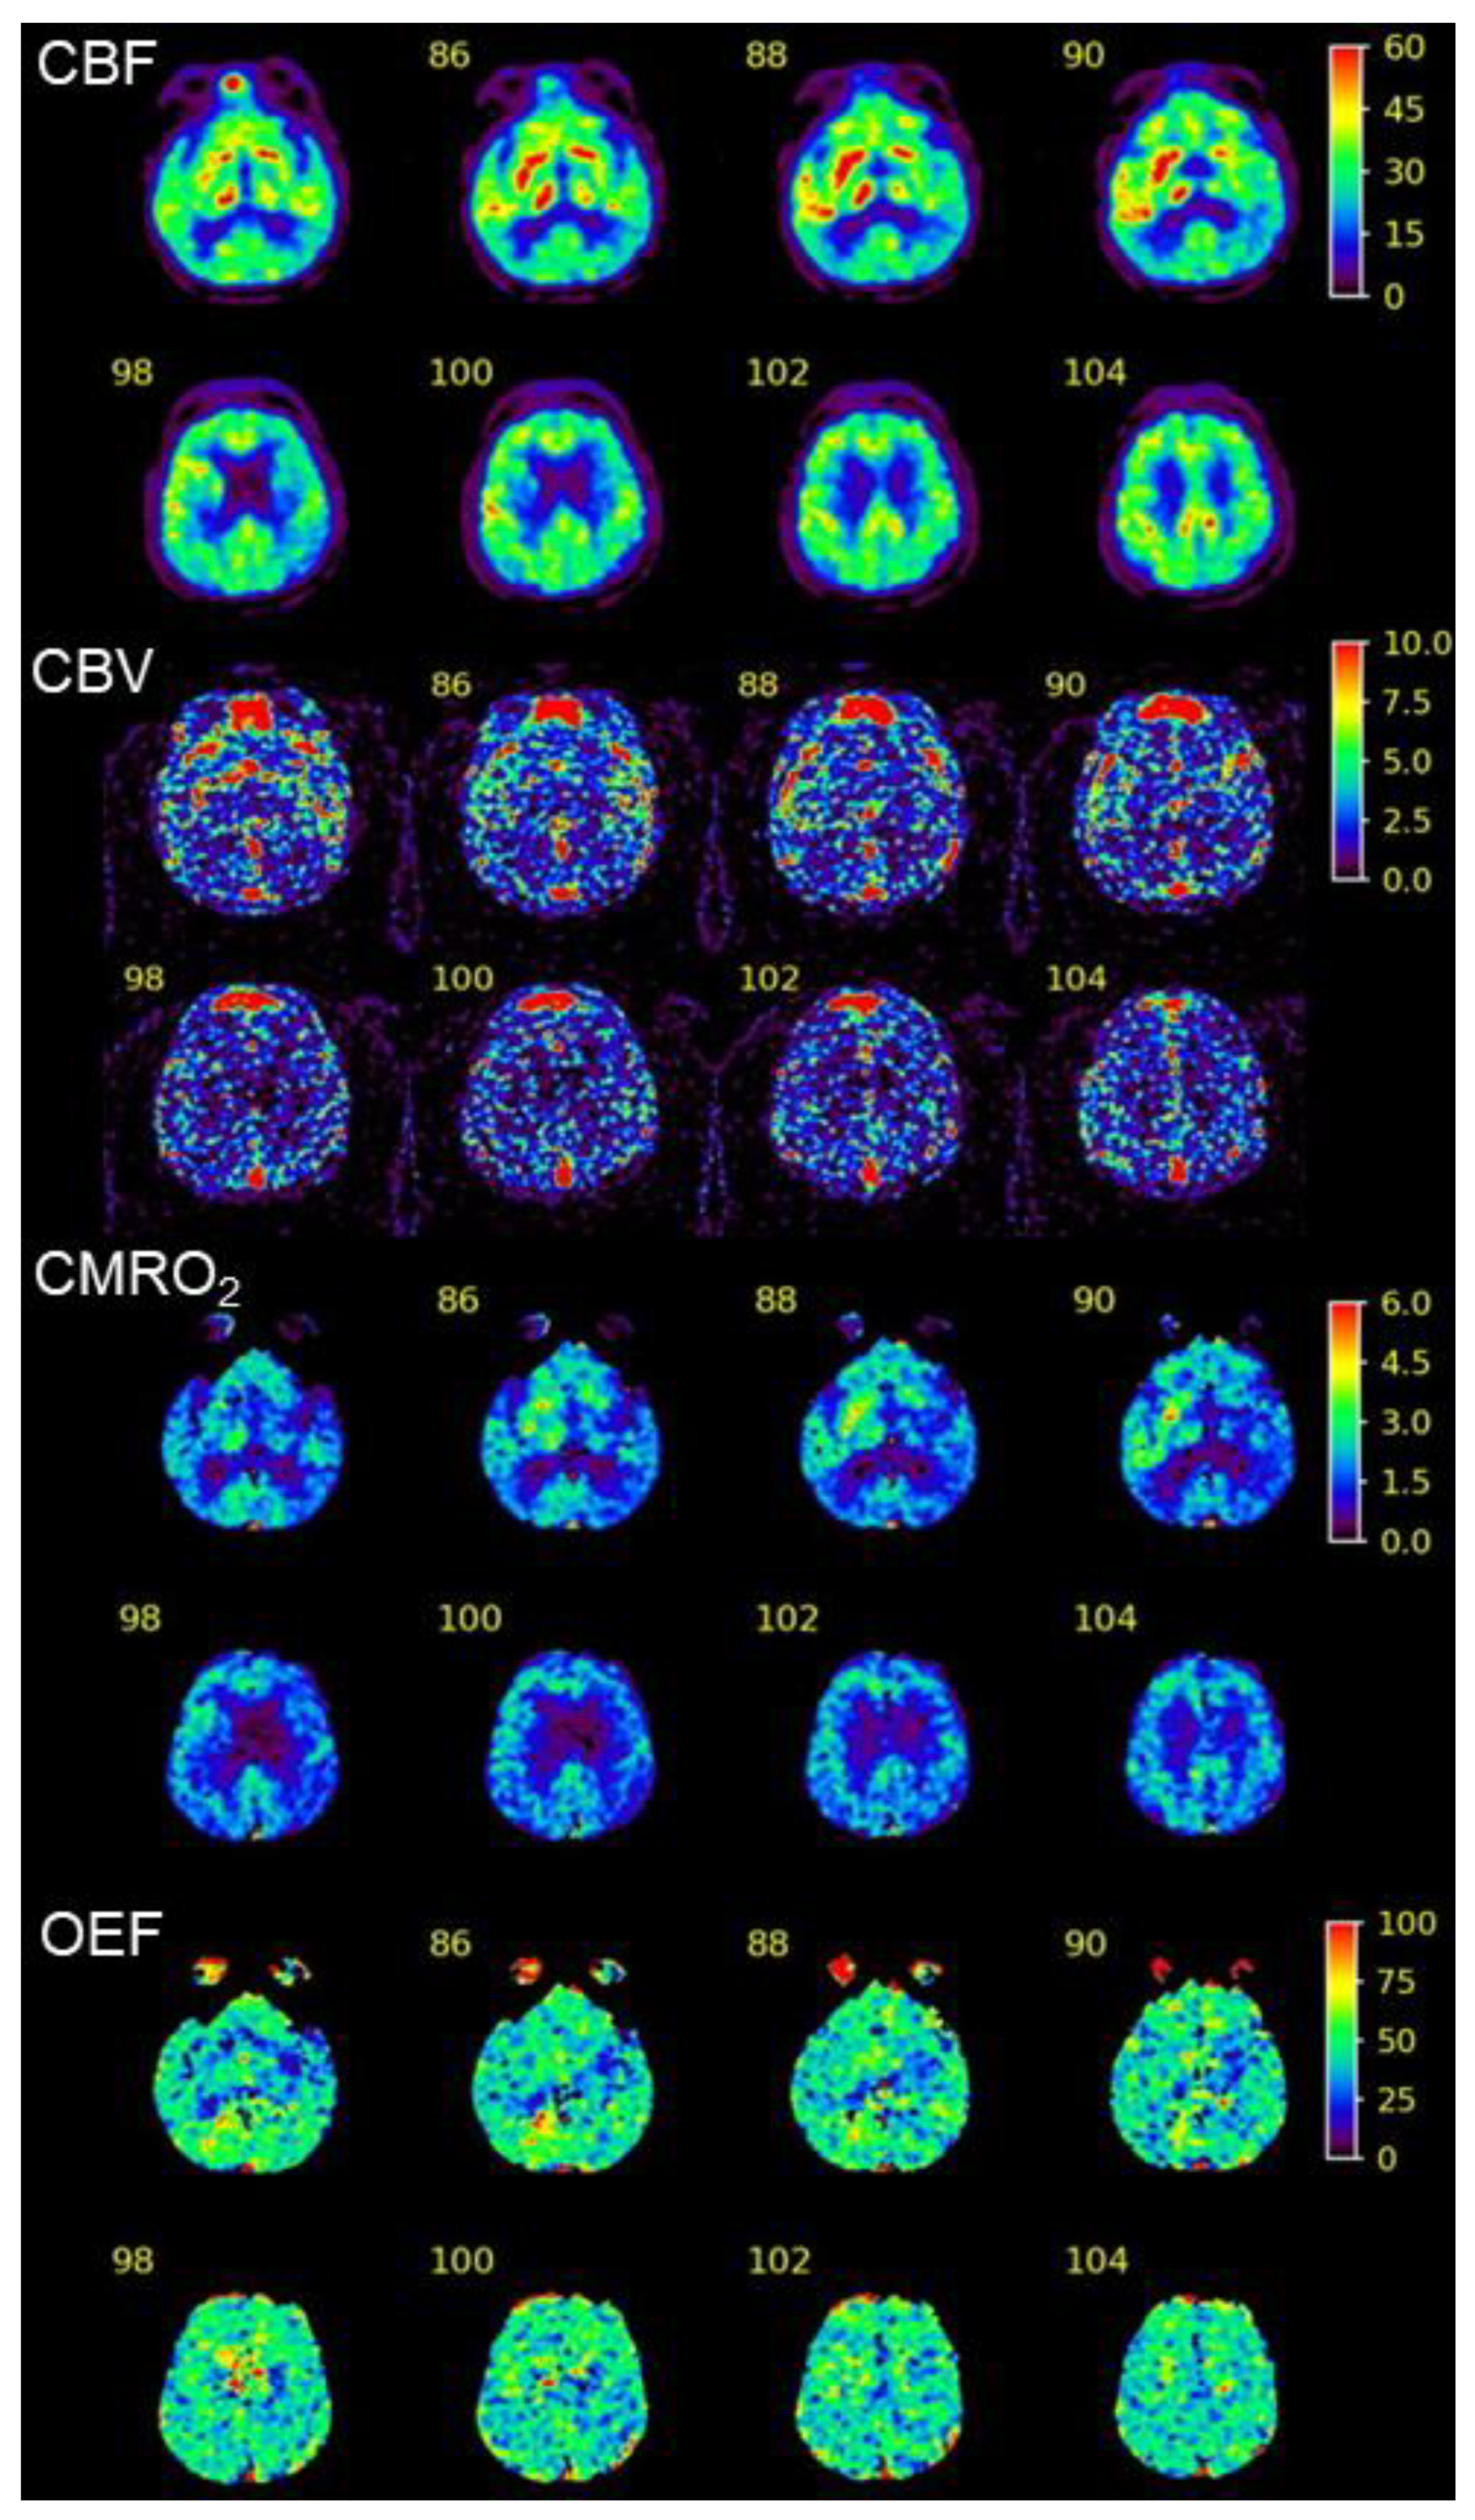

Diffusion MRI Fiber Tractography and Benzodiazepine SPECT Imaging for Assessing Neural Damage to the Language Centers in an Elderly Patient after Successful Reperfusion Therapy

2. Case Presentation